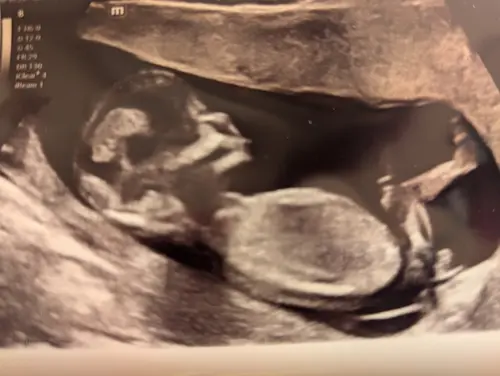

Iemand die hier iets uit kan halen? Ik zie het zelf niet..

Nog maar een keer. Niemand die iets ziet? Ook als jullie het niet kunnen zien is het wel fijn als iemand reageert want nu zie ik dat er op veel niet gereageerd wordt en het is onduidelijk waarom niet 🙊🙊

Meisje

Ik kan het niet goed zien helaas!

Nog maar een keer. Niemand die iets ziet? Ook als jullie het niet kunnen zi ...

🩷